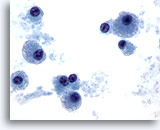

Figure 2

Neck FNA, benign cyst.

Benign squamous cells, inflammatory cells and keratin are seen in this aspirate. Note the benign metaplastic squamous cells . These are frequently found in the aspiration of cysts. 40x

Neck FNA, benign cyst.

Benign squamous cells, inflammatory cells and keratin are seen in this aspirate. Note the benign metaplastic squamous cells . These are frequently found in the aspiration of cysts.

40x